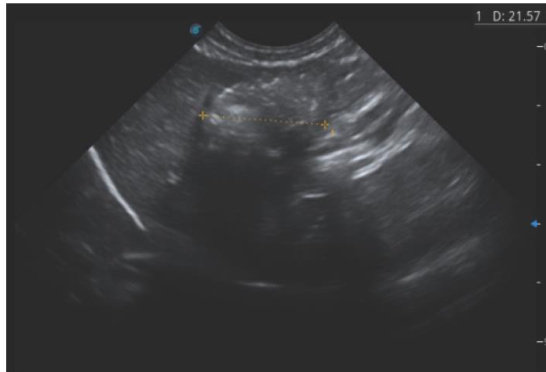

犬肠梗阻是指因误食异物、肠内容物异常或肠管运动与分泌机能紊乱导致肠腔狭窄或闭塞,以剧烈腹痛、呕吐及明显全身症状为特征的急腹症。临床上按病因可分为单纯性、嵌顿性、扭转性肠梗阻以及线性异物梗阻、肠套叠等,其中异物性肠梗阻较为常见。本文通过对两例犬误食异物所致肠梗阻的诊治进行分析与讨论。

病例1:雄性贵宾犬,2岁5月龄,体重 2.48kg 未去势,常规饲喂犬粮,已完成当年免疫。(剩余3850字)